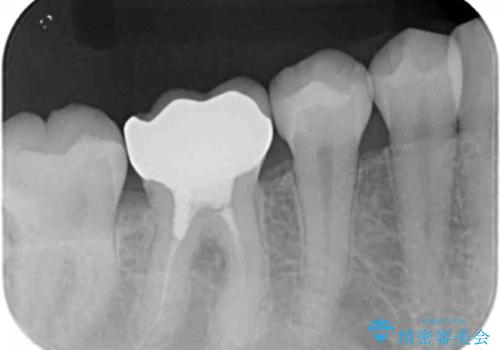

- 他の歯を治療中にレントゲン写真を撮ったところ虫歯を発見。

どうせなら1つ奥の銀歯も白くしたいとのご希望があり、2本ともセラミックにて治療をしていくことになりました。

虫歯治療に加え、奥の銀歯も同時にやり替えました。

精度の良いクラウンにやりかえることは今後の虫歯リスクを減らすことにつながります。